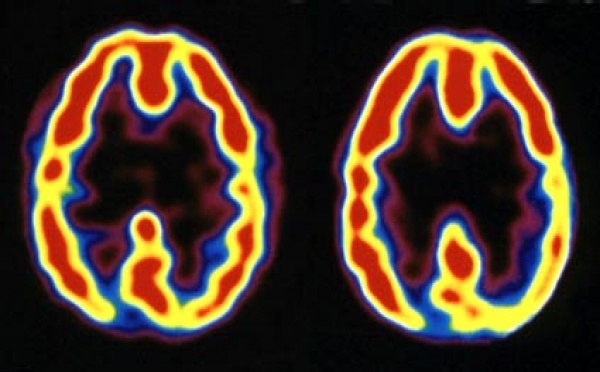

La neuroteología investiga la creación inducida de experiencias místicas - 27/06/2007

La neuroteología es una rama de la neurociencia que estudia el componente neurológico de las experiencias religiosas. Se han descubierto patrones electromagnéticos de la actividad cerebral que son activados por ciertas costumbres, como la meditación, o por otros métodos, como la inducción de impulsos electromagnéticos al cerebro, las sustancias psicodélicas e, incluso, la modificación genética. La neuroteología investiga ahora si es posible integrar de manera artificial las experiencias religiosas en nuestras vidas.